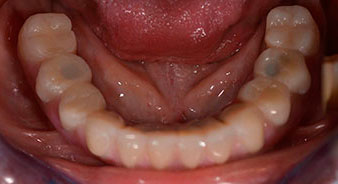

The impression and bite registration were then performed so that the dental technician could begin producing the provisional restoration immediately. This was then screwed in on the same day (Fig. 17 and 18).

Implants

Fig. 17

Fig. 18

Following the time required for the osseointegration, the final impression of the implants could be performed and the final denture produced accordingly (Fig. 19 and 20). At this point, the dentist and patient were able to decide together whether to use a ceramic or acrylic veneer and a zirconium or metal framework. In this case, Dr. Pascu’s team decided on an acrylic veneer based on the unclear prognosis for the maxillary dentition and the fact that tooth 24 is elongated. This type of veneer is generally considerably easier to adapt and can thus be subsequently altered to reflect the new situation in the maxilla.

Osseointegration

Fig. 19

Fig. 20